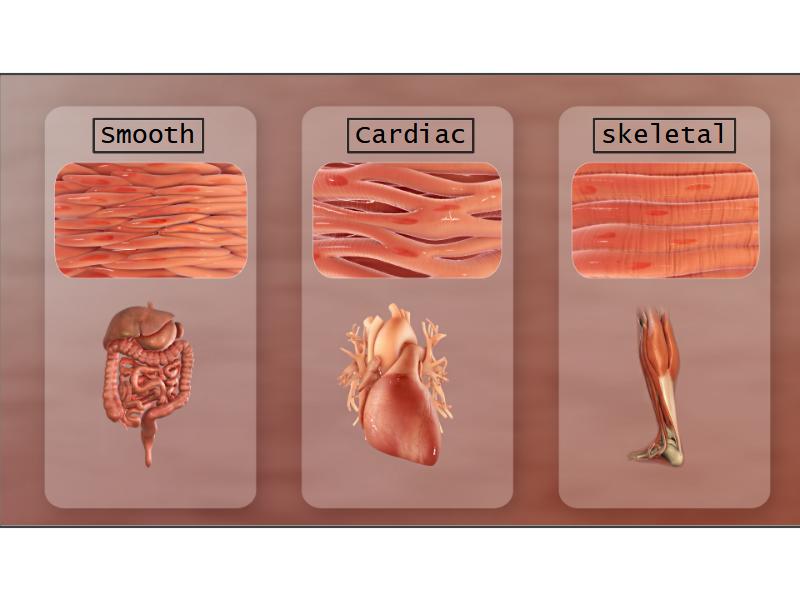

Name three types of contractile cells.